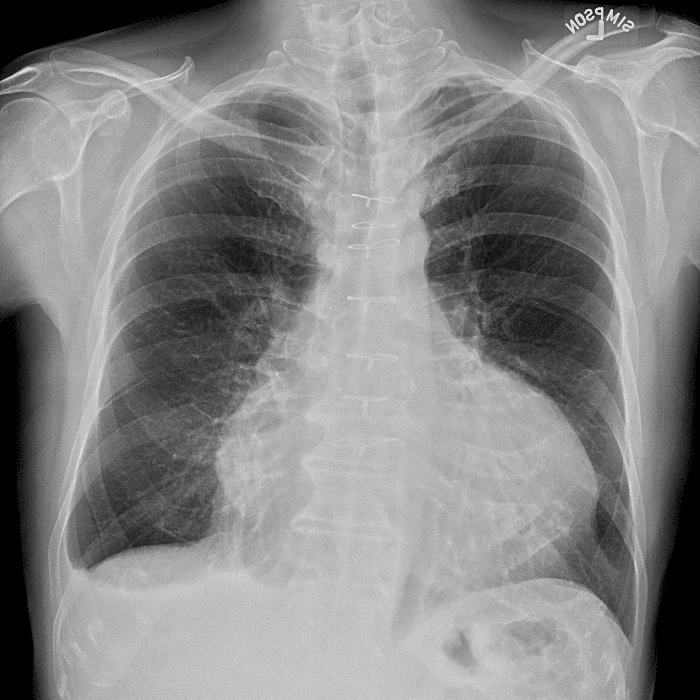

Practice Cases